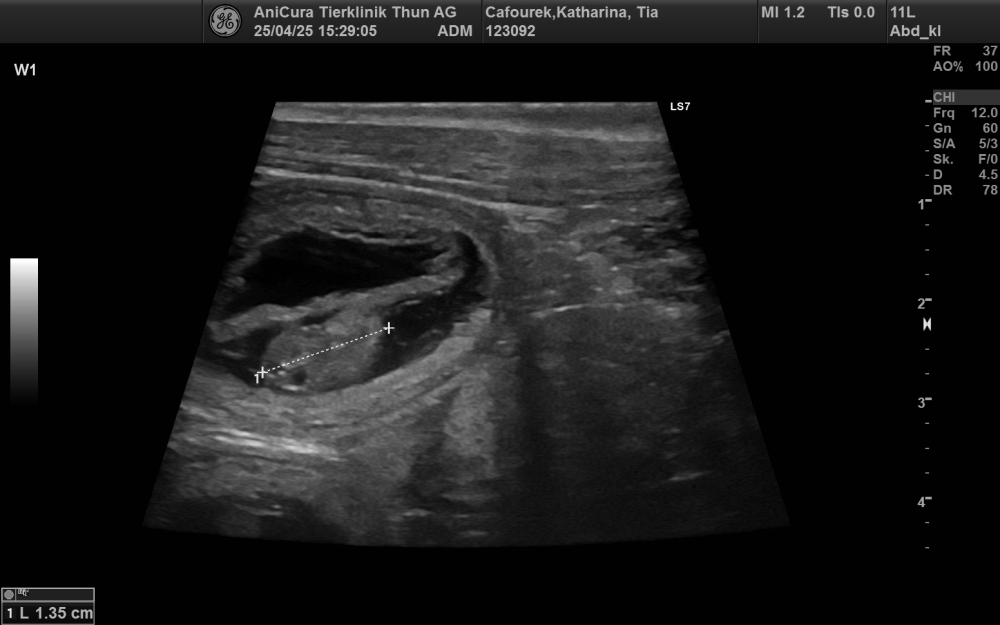

Shumbazino Hatia Feelena Tia und Hunterholm Dacapo Moyoni Mo will become parents

We are delighted for Katharina that her dream of her first breeding will soon come true and we cross all fingers for Tia having an uncomplicated pregnancy.